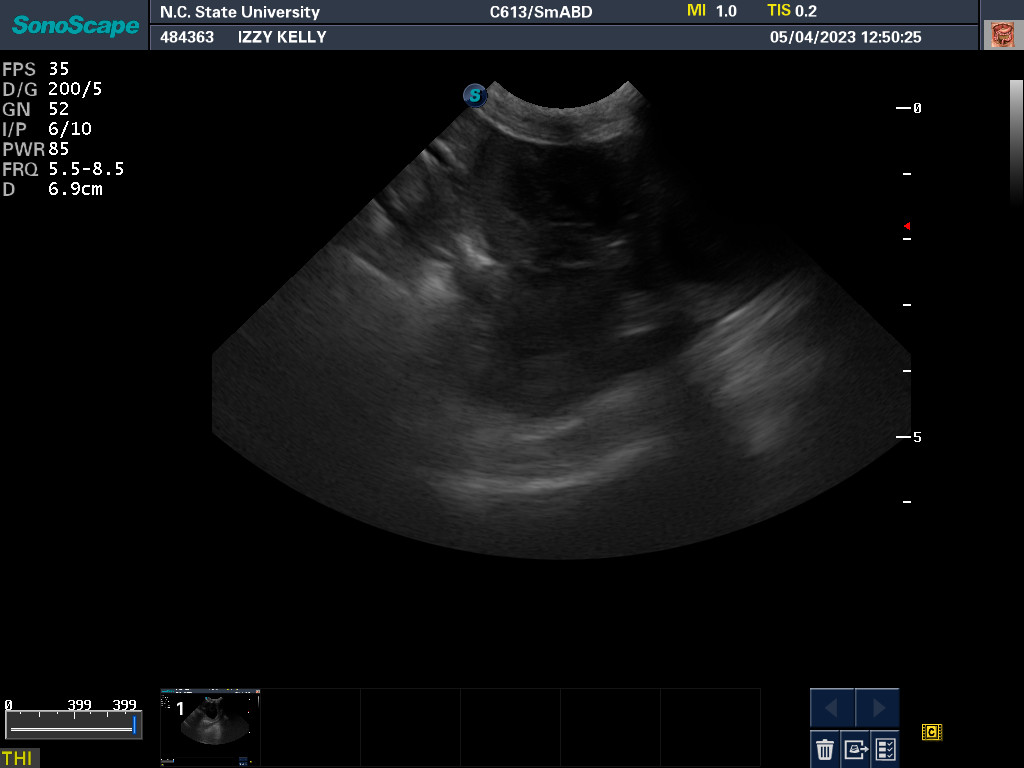

NC State University for an autopsy.